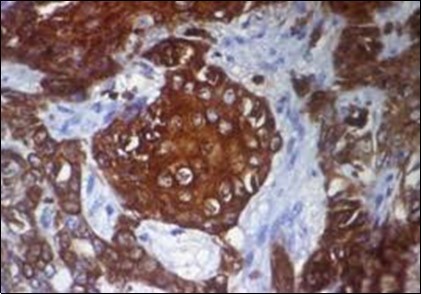

Granular arrangement of malignant cells and intercellular bridges are conspicuous with the demonstration of nuclear atypia, pleomorphism, prominent mitosis and tumour necrosis. A peripheral palisade is discernible within the cellular aggregates. Mitotic figures are common and can be quantified as up to 12 mitosis/ high power field. Tumour differentiation can prominently be of the ductal category with the demonstration of intra-cytoplasmic lumina. Comedo type tumour necrosis is evident along with foci of squamous differentiation The neoplasm is reactive to periodic acid Schiff ‘s (PAS) stain. (Figure 1, Figure 2, Figure 3, Figure 4, Figure 5, Figure 6, Figure 7, Figure 8, Figure 9, Figure 10, Figure 11, Figure 12, Figure 13.

Figure 12.Immune reactivity to cyto-keratin (CK7) in eccrine porocarcinoma(24).

Figure 13.Immune reactivity to CK6 in eccrine porocarcinoma(25).

Eccrine porocarcinoma is immune reactive to carcino-embryonic antigen (CEA) and cyto-keratins 6 and 7(CK6,7), epithelial membrane antigen (EMA) and non reactive to S-100 protein. Reactivity to cyto-keratin 20 (CK20) assists the diagnosis in instances with indeterminate histology. Immune reactive p63, CK5 , weak P40 and non reactive GATA3 are additionally elucidated by the tumour 2, 3, 4.